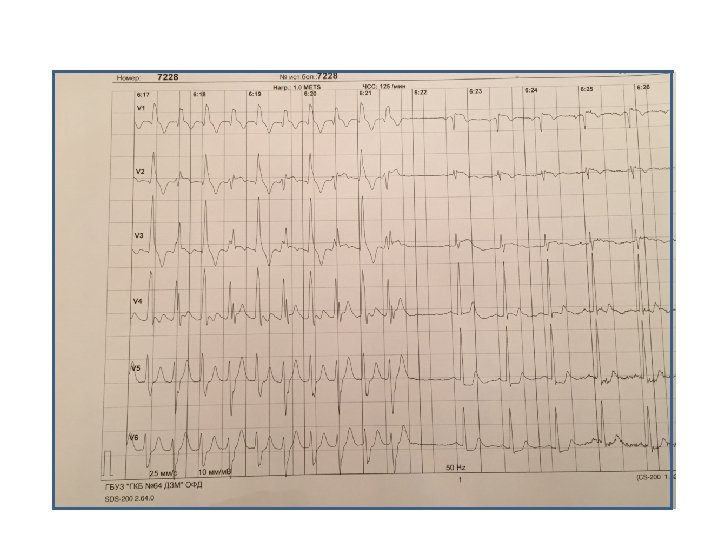

Пациент Б. , 58 лет Направление: диагностика ИБС

Пациент Б. , 58 лет Направление: диагностика ИБС